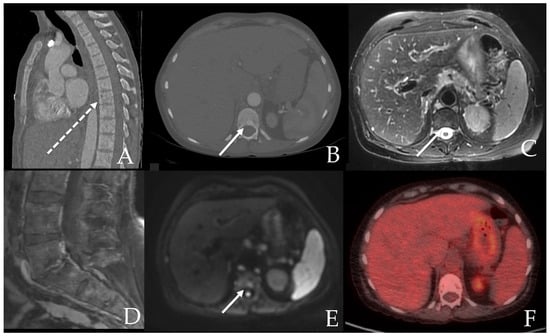

6.1. Skeletal

- Leone, A.; Criscuolo, M.; Gullì, C.; Petrosino, A.; Carlo Bianco, N.; Colosimo, C. Systemic mastocytosis revisited with an emphasis on skeletal manifestations. Radiol. Med. 2021, 126, 585–598. [Google Scholar] [CrossRef] [PubMed]

- Fritz, J.; Fishman, E.K.; Carrino, J.A.; Horger, M.S. Advanced imaging of skeletal manifestations of systemic mastocytosis. Skelet. Radiol. 2012, 41, 887–897. [Google Scholar] [CrossRef] [PubMed]

- Roca, M.; Mota, J.; Giraldo, P.; García Erce, J.A. Systemic mastocytosis: MRI of bone marrow involvement. Eur. Radiol. 1999, 9, 1094–1097. [Google Scholar] [CrossRef]

- Ozturk, K.; Cayci, Z.; Gotlib, J.; Akin, C.; George, T.I.; Ustun, C. Non-hematologic diagnosis of systemic mastocytosis: Collaboration of radiology and pathology. Blood Rev. 2021, 45, 100693. [Google Scholar] [CrossRef]